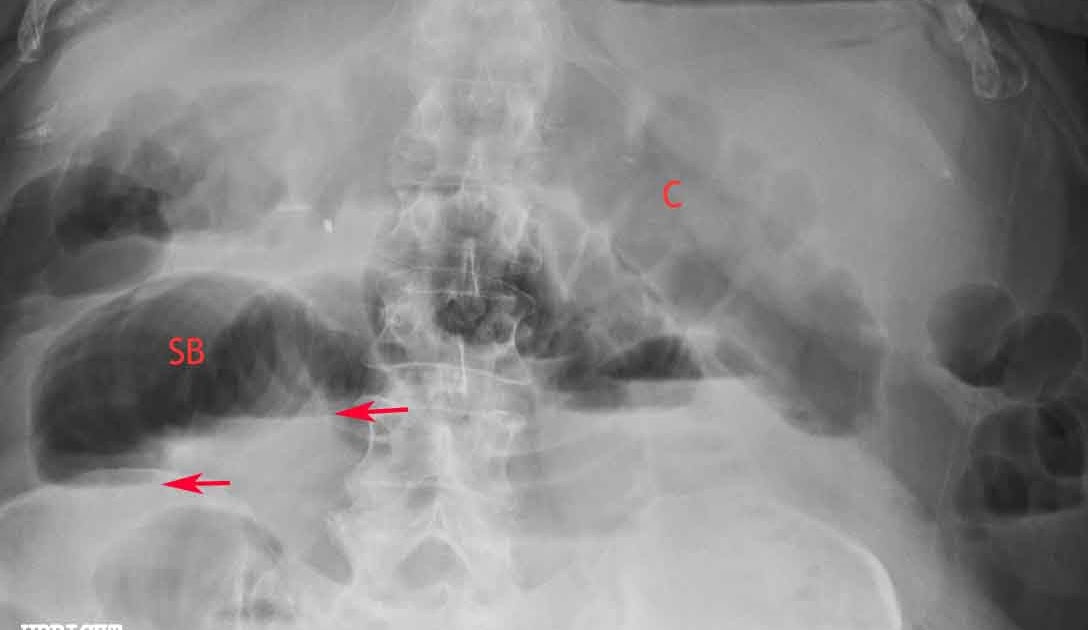

Air Fluid Levels Bowel X Ray . Dilated loops of small or large bowel—obstruction, ileus or inflammation. Loops proximal to the obstruction soon become dilated with air and/or fluid. Large bowel obstruction (lbo) is often impressive on imaging, on account of the ability of the large bowel to massively distend. Intestinal obstruction is a clinical scenario commonly encountered by colorectal surgeons, 1 and it is important to understand. Citation, doi, disclosures and article data. The bowel reacts to a mechanical obstruction in more or less predictable ways. (b) upright abdominal radiograph shows multiple air fluid levels (large and small arrows), fluid levels greater than 2.5 cm (large arrows), and fluid levels of unequal heights. Erect chest radiographs can also be used to screen for.

(b) upright abdominal radiograph shows multiple air fluid levels (large and small arrows), fluid levels greater than 2.5 cm (large arrows), and fluid levels of unequal heights. Dilated loops of small or large bowel—obstruction, ileus or inflammation. Erect chest radiographs can also be used to screen for. The bowel reacts to a mechanical obstruction in more or less predictable ways. Large bowel obstruction (lbo) is often impressive on imaging, on account of the ability of the large bowel to massively distend. Intestinal obstruction is a clinical scenario commonly encountered by colorectal surgeons, 1 and it is important to understand. Citation, doi, disclosures and article data. Loops proximal to the obstruction soon become dilated with air and/or fluid.